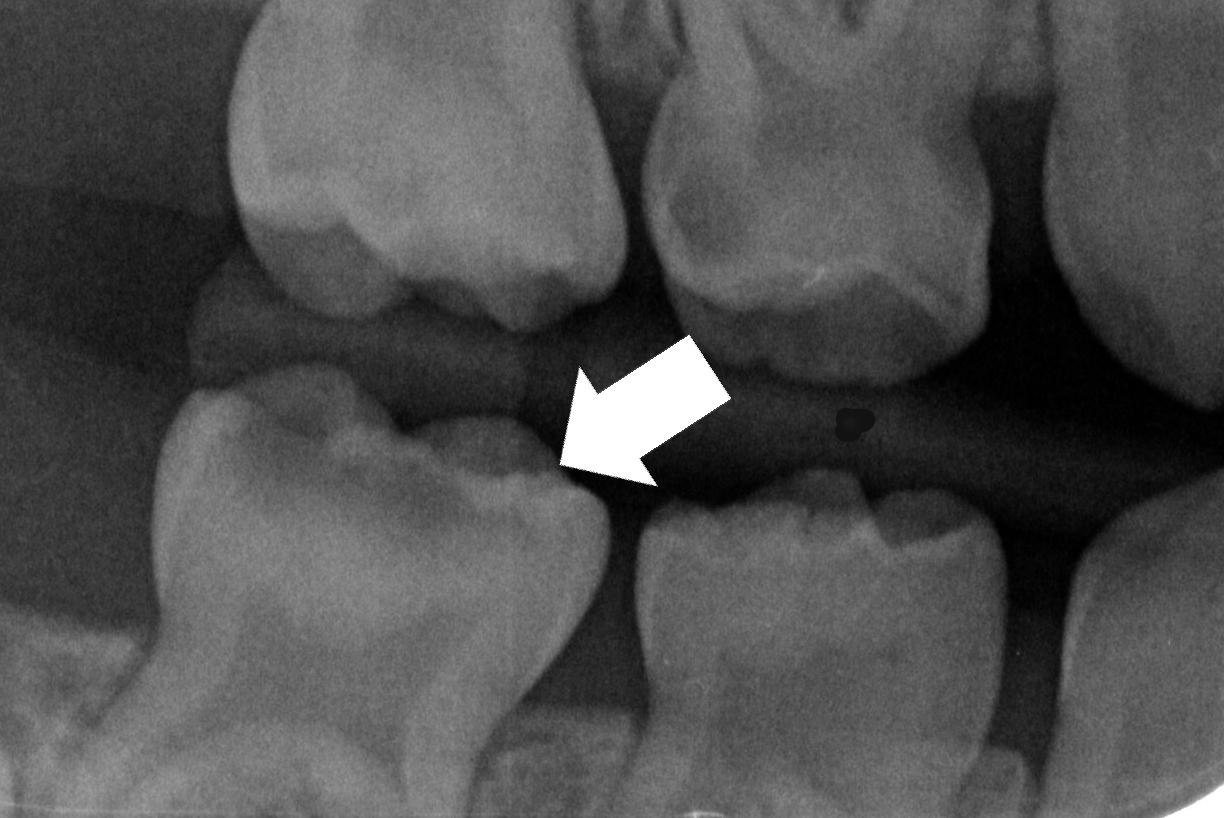

Schritt 3: Präparierter Zahn - Karies entfernt; verfärbtes, nicht kariös erweichtes Dentin wird stets belassen!